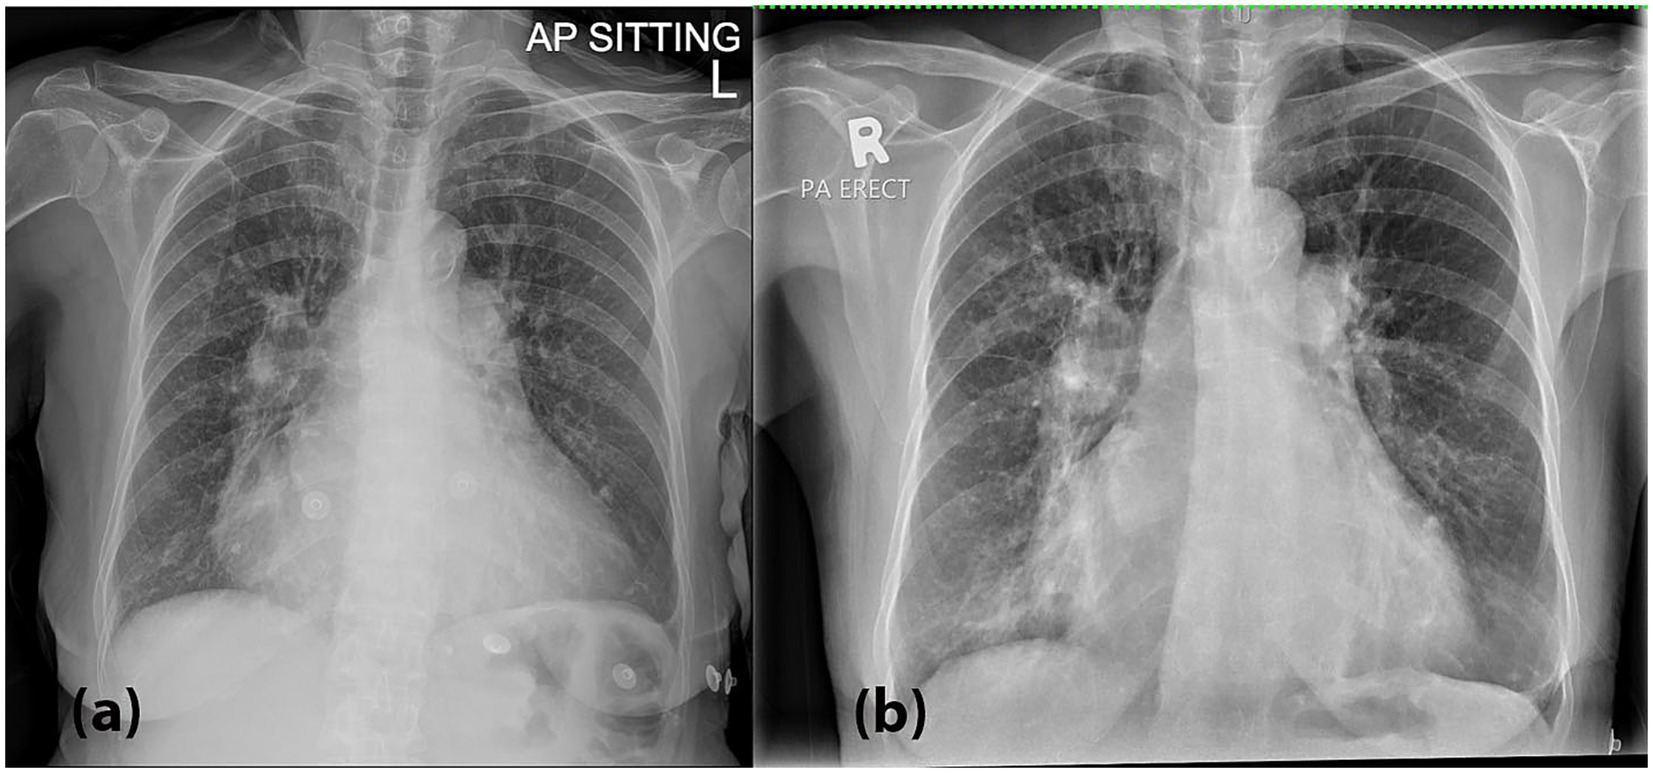

Upon arrival at the Emergency Department, she appeared breathless but was not using accessory muscles and remained alert. She was febrile (39.6 °C), tachypneic (respiratory rate of 24–26 breaths/min) and hypoxemic with peripheral oxygen saturation of 92% on room air. Her blood pressure and heart rate were unremarkable; BP 119/68 HR 90 bpm. On physical examination, lung auscultation revealed crepitations localized to the right lower lung zone. Arterial blood gas (ABG) analysis demonstrated type 1 respiratory failure, while inflammatory markers including PCT (0.04 ng/mL), CRP (2.52 mg/dL) white blood cell count (6.6 × 109/L) were within normal limits. She tested negative for COVID-19. A chest radiograph (Figure 1a) performed on presentation demonstrated features suggestive of pulmonary edema. In correlation with the clinical presentation and laboratory results, the initial working diagnosis was community-acquired pneumonia (CAP), and the patient was subsequently admitted for empirical antibiotic therapy (intravenous augmentin 1.2 g QID and oral azithromycin 500 mg OD) targeting both typical and atypical respiratory pathogens. Her previous diuretics medications were also on board, which were oral spironolactone 12.5 mg OD and furosemide 20 mg PRN.

Figure 1

X-ray images of a chest. The left image (a) shows an AP sitting view, highlighting the lungs and heart. The right image (b) depicts a PA erect view, offering a different perspective of the thoracic area.

Figure 1. (a) A chest radiograph (CXR) performed on presentation demonstrated bilateral hilar opacities with peribronchial cuffing, along with radiographic features suggestive of pulmonary edema, including fluid in the right horizontal fissure and Kerley B lines, especially in the right lower zone. These findings are suggestive of an active pulmonary infection superimposed on acute pulmonary edema. (b) A repeat CXR on Day 3 showed worsening bilateral hilar and lower zone opacities, along with persistent peribronchial cuffing.

During hospitalization, the patient experienced recurrent fever spikes and oxygen desaturation, necessitating anti-pyretic and supplemental oxygen via nasal prong 3 L/min. A repeat chest radiograph on Day 3 (Figure 1b) showed worsening bilateral hilar and lower zone opacities, along with persistent peribronchial cuffing. Laboratory investigations at that point revealed thrombocytopenia and leucocytopenia, with infective screenings (blood and sputum bacterial and tuberculosis cultures, PCT, CRP, dengue serology, BFMP) yielded negative results.